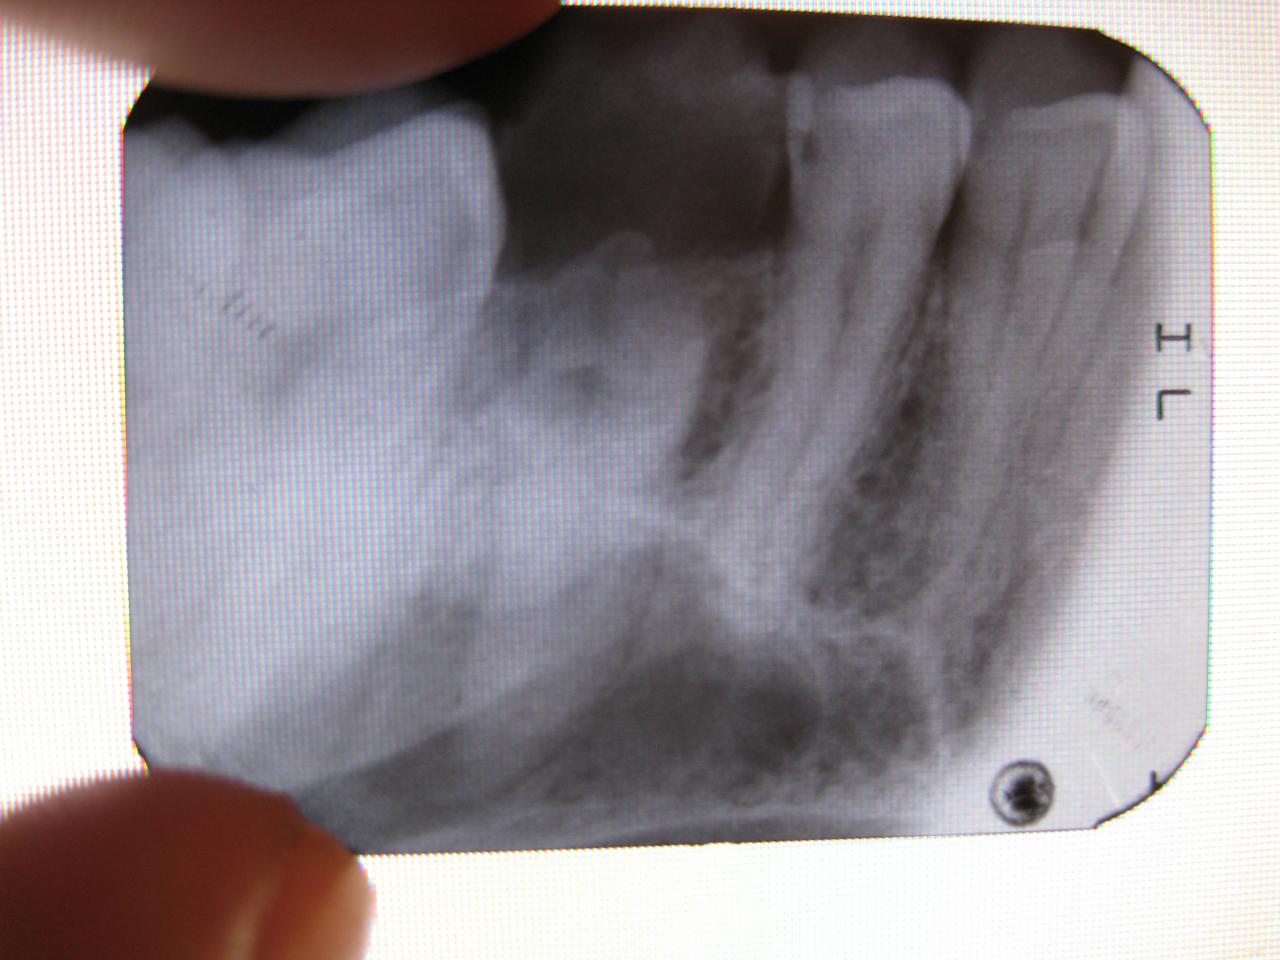

Уважаемые эскулапы, подскажите пожалуйста шанс на "неудаление" в данном случае)))

Если над десной меньше 1 мм тканей зуба - удаляйте.

По ходу тут разрушение под десной миллиметра на 3.

смысл его лечить? никакая реставрация или коронка с вкладкой не выживут - слишком разрушен под десну....